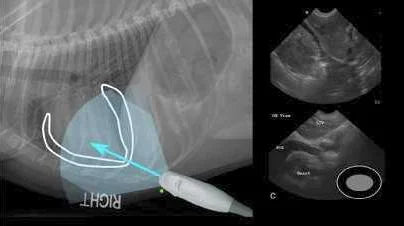

Global FAST: Un Enfoque Rápido para Detectar As...

El protocolo Global FAST se ha convertido en una herramienta esencial en emergencias veterinarias, permitiendo la detección rápida de ascitis, derrame pericárdico y otros signos críticos en pacientes con trauma...